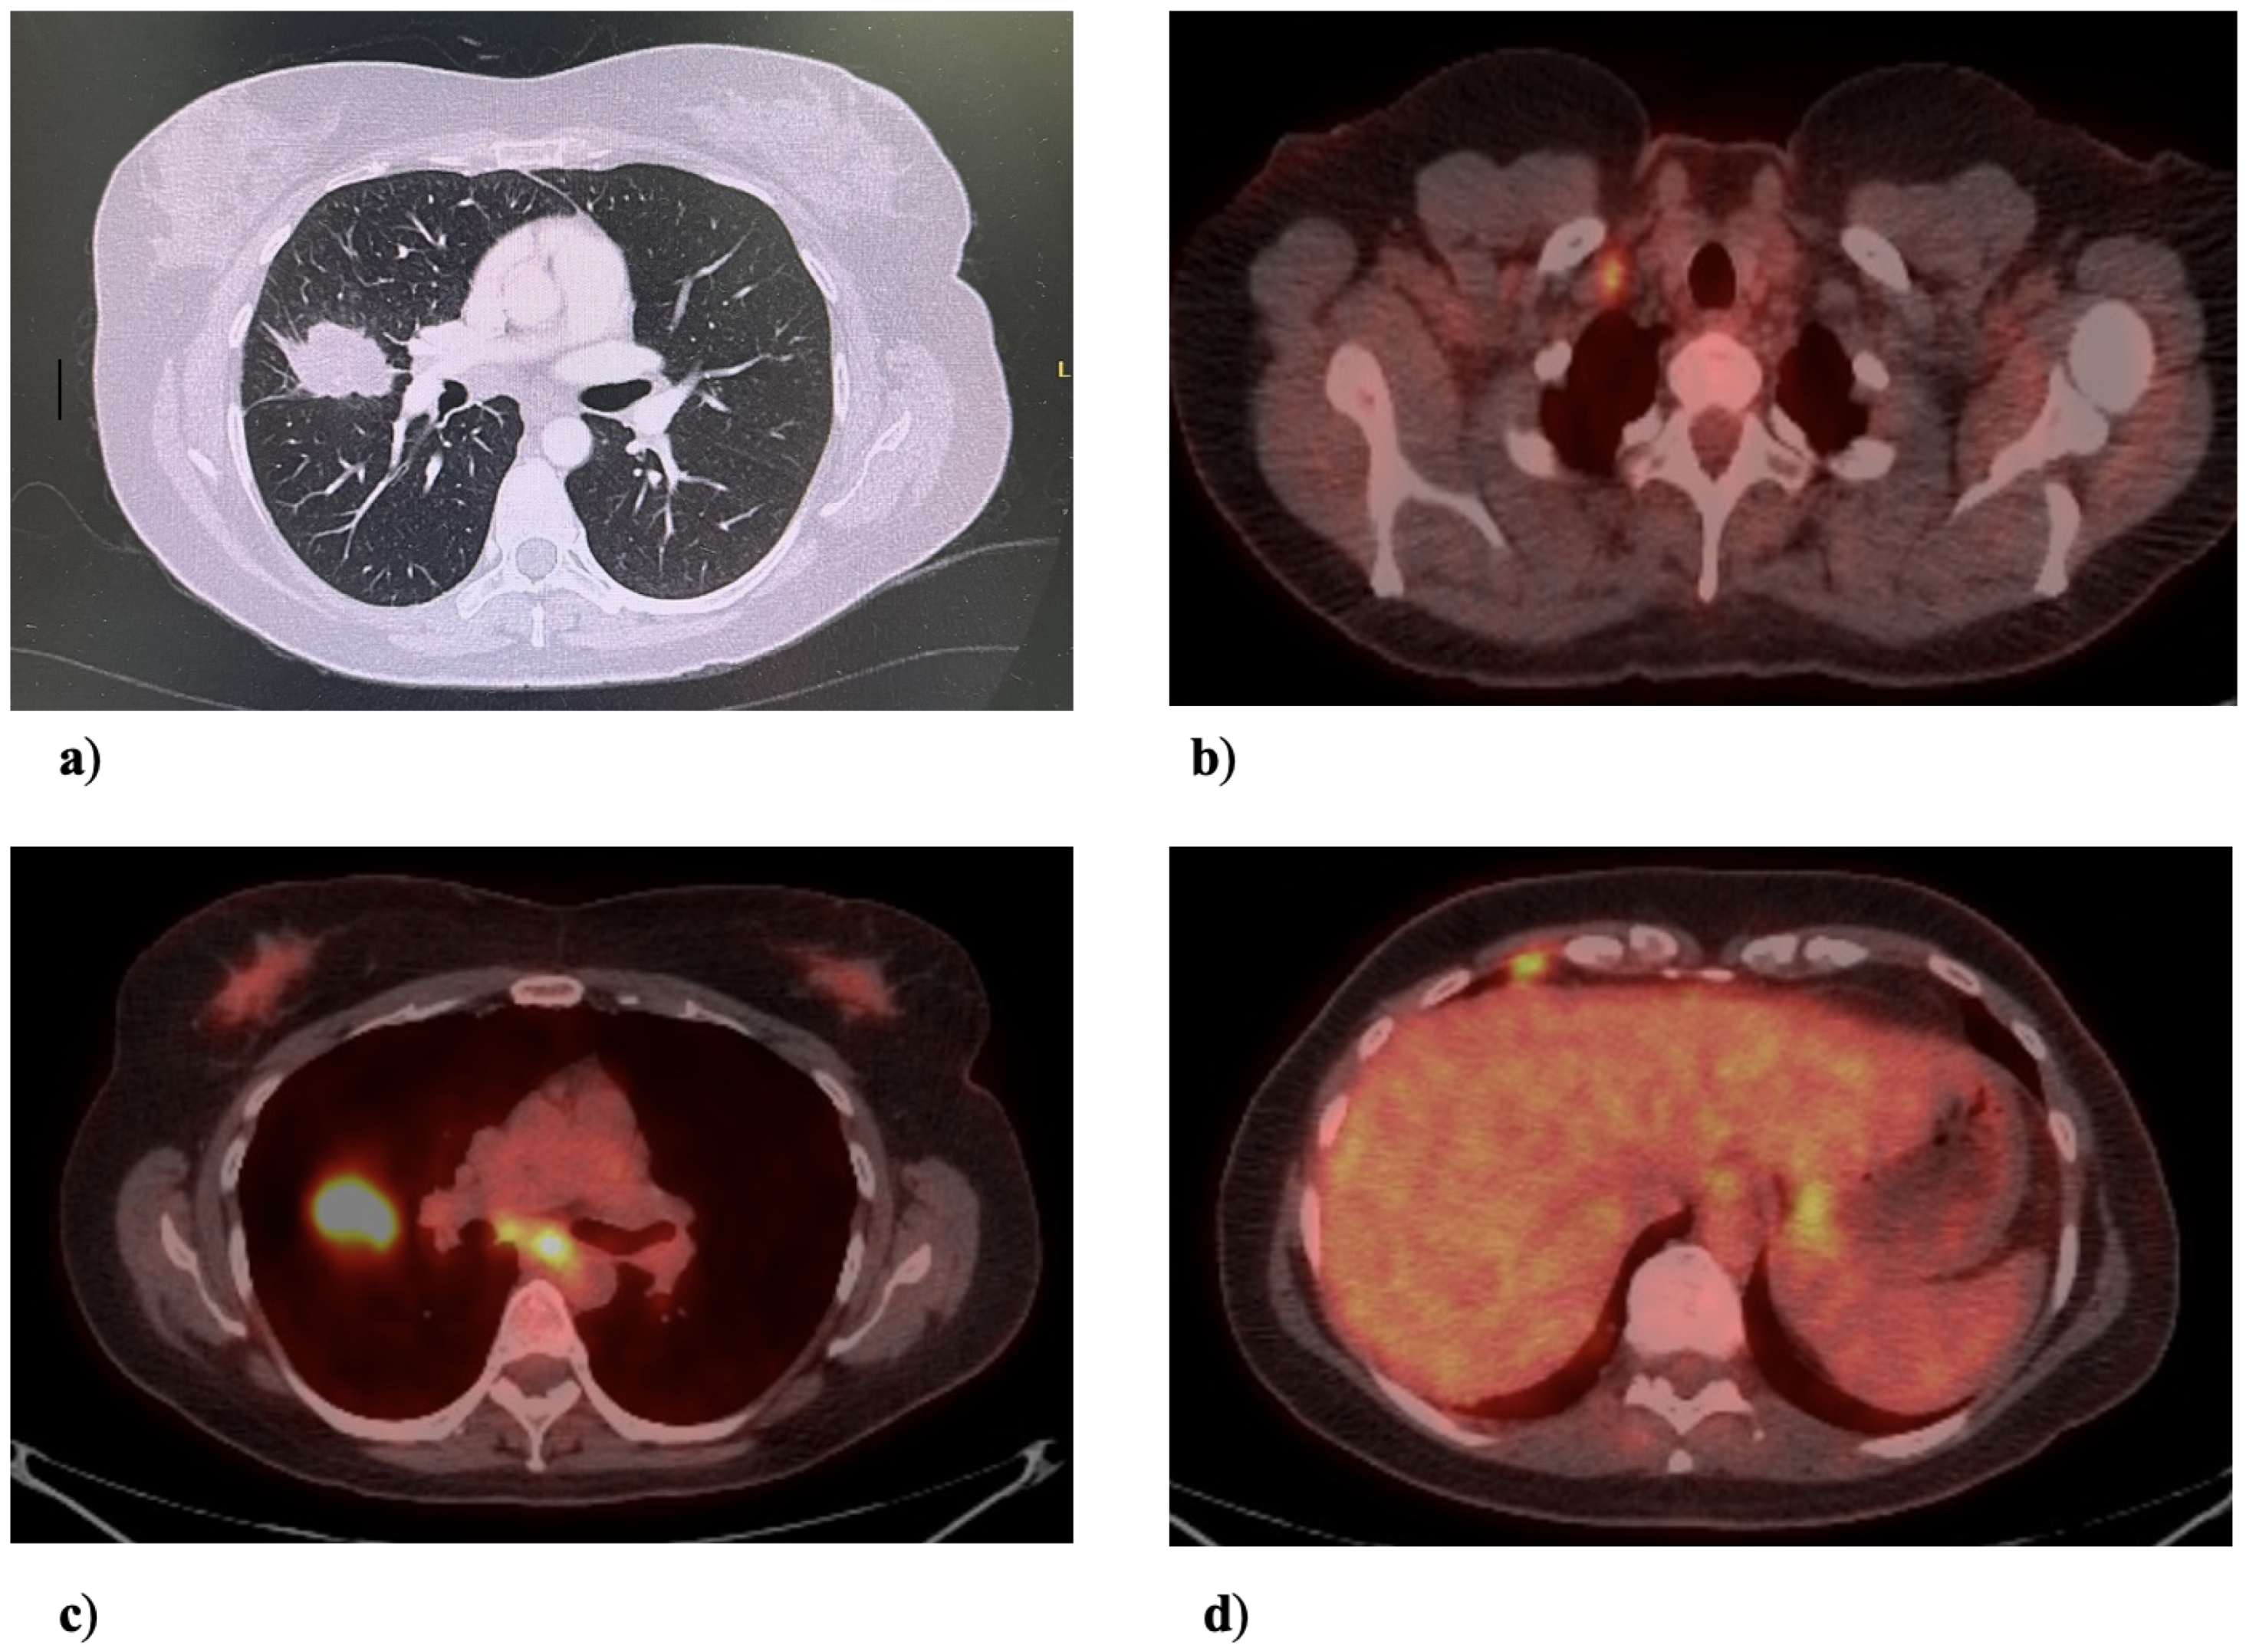

Five and a half years after initiating systemic therapy, a surveillance CT on 26 October 2022 demonstrated progression at the site of the primary tumor. A PET scan on 2 February 2023 suggested the pleural metastatic and nodal disease had undergone a complete radiographic response but showed activity at the initial primary site (Figure 3). After review by a multidisciplinary tumor board, a decision was made to proceed with anatomical resection.

Figure 3. PET scan, 2 February 2023. The suspected site of recurrent disease in the right middle lobe was intensely FDG-avid. The lesion metabolically measured 3.6 × 1.9 cm. No other FDG-avid primary nodule or mass was seen. There was no FDG-avid thoracic adenopathy.